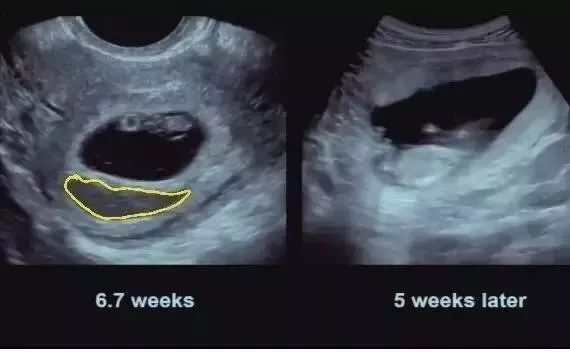

血種が消えるまでの12週間 絨毛膜下血腫 を抱えて挑んだ私の出産 たまひよ